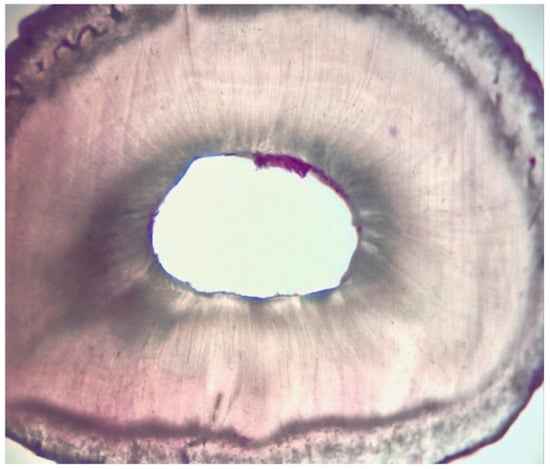

2.3. Assessment of Root Canal Cleanliness

| Grading | |

|---|---|

| I | presence of debris within the area |

| II | presence of debris in more than 50% of the entire area |

| III | presence of debris in more than 25% of the entire area |

| IV | absence of debris or presence of debris in less than 25% of the entire area |

| Score | I | II | II | I | II | III | II | II | II | I | II | I | II | III | II | II | III | II | I | II |